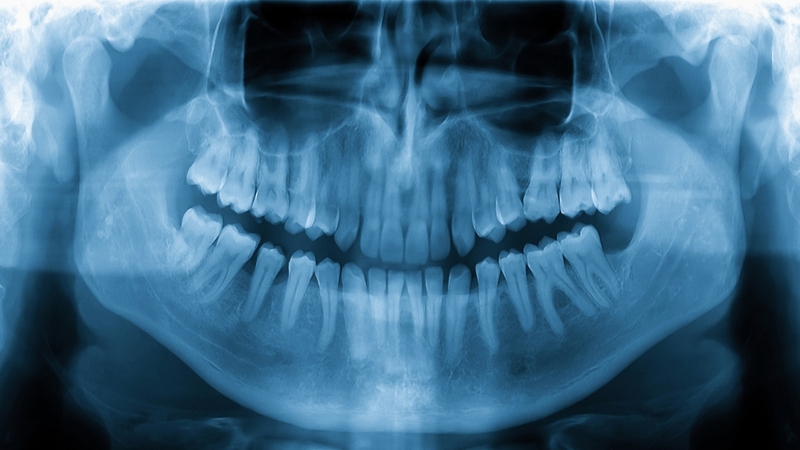

Ở người trưởng thành, răng khôn (răng số 8) là răng hàm lớn thứ ba và mọc sau cùng trong cung hàm. Nếu hệ răng phát triển đầy đủ, một người thường có 4 răng khôn, bao gồm 2 răng ở hàm trên và 2 răng ở hàm dưới. Những chiếc răng này mọc phía sau răng hàm lớn thứ hai (răng số 7) và thường xuất hiện trong giai đoạn từ 17 đến 25 tuổi, khi xương hàm đã gần như phát triển hoàn chỉnh.

Giải đáp chi tiết răng khôn có mấy cái